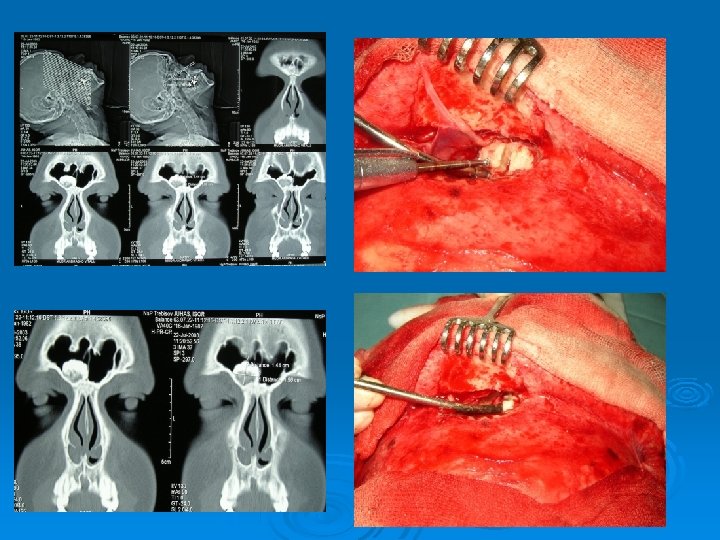

Kazuistika č. 1 – 24 ročný pacient I. J. Subj: asi 2 roky bolesti hlavy, opakovane sinusitídy, polyvalentná alergia, liečený na hypertenziu a DM I typu, otec nosové polypy CT PND: 3 cm osteóm na spodine ľ. čelovej dutiny v oblasti vývodu, cysta ľavej maxil. dutiny, závojovanie ľavých ethmoidov Op. liečba: osteoplastická operácia ľ. čelovej dutiny, FESS vľavo ( STA, etmoidektómia, frontotómia) Histológia: Osteoid osteoma

Kazuistika č. 2 – 35 ročný pacient R. Š. Subj: 3 -4 mesiace únava, bolesti hlavy, pocit tlaku, prekonal boreliózu, alergia na pele a prach CT PND: odliatkový osteóm ľavej čelovej dutiny Op. liečba: osteoplastická frontálna sinusotómia vľavo Histológia: Osteoid osteoma

Kazuistika č. 3 – 68 ročná pacientka M. L. Subj: 3 -4 mesiace úporné bolesti hlavy, pocit tlaku v čele CT PND: 2 osteómy mediálnej časti ľavej čelovej dutiny, väčší 1, 5 cm takmer blokuje vývod Op. liečba: endoskopický prístup - Draf II vľavo Histológia: Osteoid osteoma